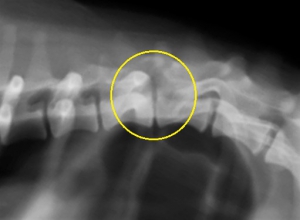

椎間板ヘルニアを疑う患者さんが来院した場合には、その程度にもよりますが、レントゲン検査がまず最初に必要な検査となるでしょう。ところが、この検査では椎間板ヘルニアの確定診断にはなりません。

それは「ヘルニア」はレントゲンに映り難く、診断精度が高くないためにその存在を疑うことはできても診断はできません。では、何でレントゲン検査をするの?と思われると思いますが、これは除外診断といって、同じような症状を起こす骨折や脊椎炎、腫瘍など椎間板ヘルニア以外の可能性はないかどうか確認するためのものです。

下の写真が椎間板ヘルニアのレントゲン写真です。黄色丸の中に「ヘルニア」があります。よく目を凝らしてご覧ください。

いかがでしたでしょうか?何か見えましたでしょうか?実は何も見えていません。ところが、ここにはかなり重度の椎間板ヘルニアがあるということが分かりました。